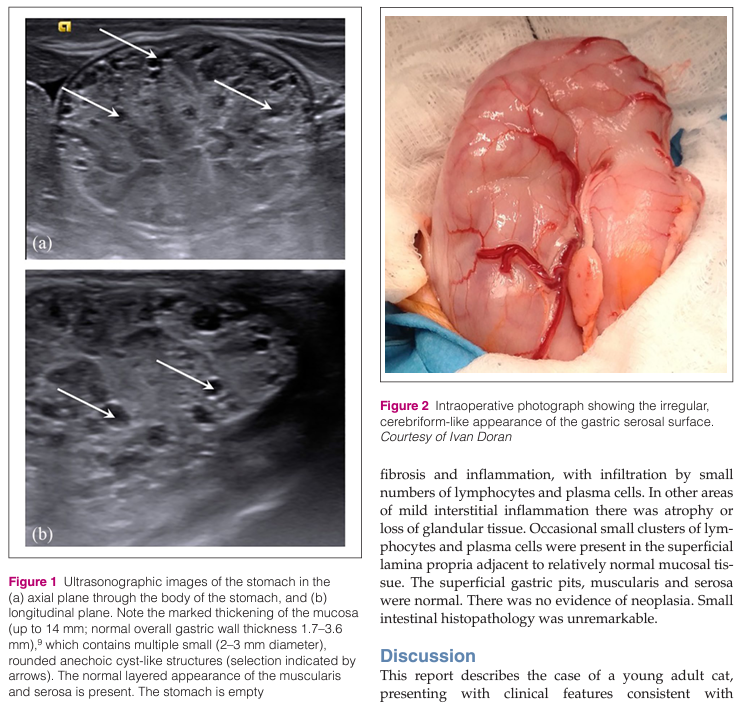

거대 비대성 위염을 보이는 메네트리예 병의 고양이에서의 첫 번째 진단 보고 케이스이다. Ménétrier-like disease

대부분 무에코성 cyst가 다발하여 관찰되는 특징이 있지만 사람의 증례에서는 cyst가 없는 양상도 존재한다고 알려져 있다. 아직 고양이 case가 보고된 게 이 케이스 말고는 없기 때문에 실제 증례에서는 어떤 차이가 있을지 구분되어야 한다.